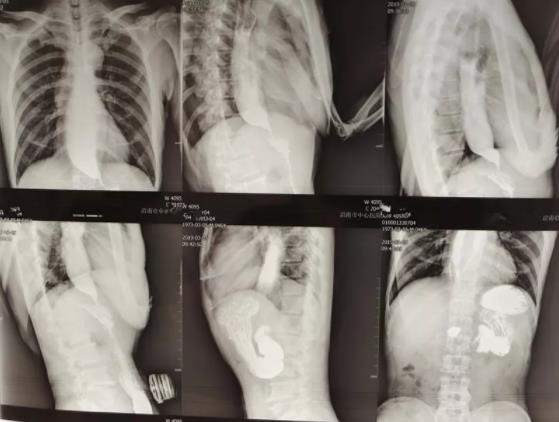

患者男性,46岁,一年前没有任何原因的出现反胃,伴随有进食哽咽感,固体食物尤为明显。并且偶尔有反酸、嗳气。在当地诊所反复口服中药治疗后效果不佳,随后到市中心医院消化内科就诊,在门诊行上消化道造影提示贲门失弛缓症。

患者入院后,消化内科内镜团队给予患者抑酸、促动力治疗后症状有所缓解,但仍有进食哽咽感。为进一步解决患者症状,内镜团队为患者在全麻下行经内镜下肌切开术(POEM)。术后患者恢复情况良好,无出血、感染、气胸等并发症。